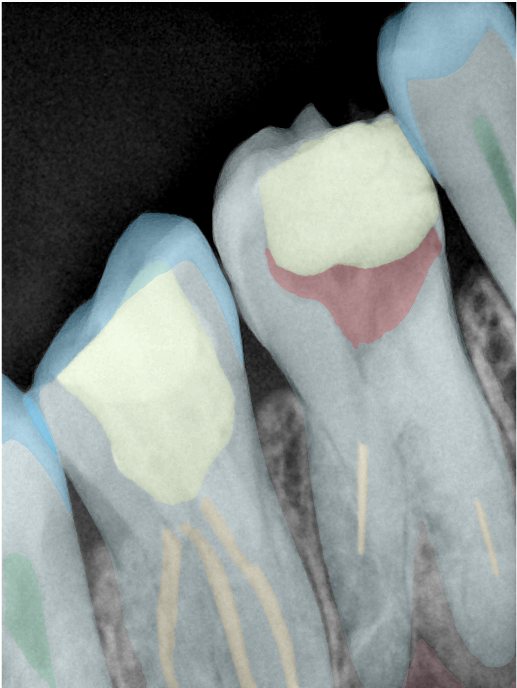

CR/DR 牙齿分割阶段记录

当前进展

- 完成了 CR/DR 牙齿相关分割训练

- 当前结果已经达到阶段预期,但仍有细节问题需要继续处理

相关测试

遇到的问题

- 训练过程中出现过 mask 下移问题

- 部分结果会出现 box 填充异常

- mask 边缘仍然有比较明显的锯齿感

参考

第二版算法问题测试